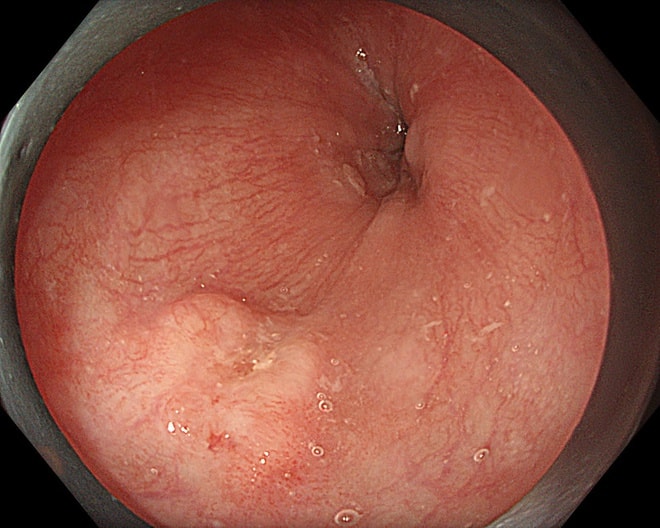

Hình ảnh tổn thương thực quản của bệnh nhân.

Một bệnh nhân 63 tuổi đã được phát hiện ung thư thực quản giai đoạn sớm nhờ công nghệ này và điều trị thành công, xuất viện sau 2 ngày.

Trong một trường hợp khác, bệnh nhân 67 tuổi được phát hiện tổn thương qua nội soi công nghệ cao. Tuy nhiên, qua đánh giá chuyên sâu, bác sĩ xác định tổn thương đã vượt chỉ định điều trị nội soi và chuyển sang phẫu thuật.

Kết quả mô bệnh học sau đó xác nhận ung thư đã xâm lấn dưới niêm mạc, phù hợp với chỉ định ngoại khoa.

Thực tế này cho thấy vai trò quan trọng của nội soi công nghệ cao kết hợp với kinh nghiệm lâm sàng trong việc đánh giá chính xác giai đoạn bệnh, từ đó đưa ra phương pháp điều trị phù hợp, tối ưu.